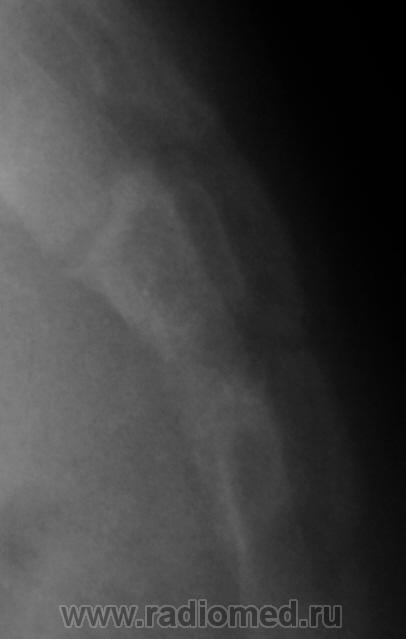

Ребенок направлен хирургом на рентгенографию крестца и копчика, Накануне ребенок упал. Приводится только боковая рентгенограмма, так как рентгенограмма, выполненная в прямой проекции не информативна.

Вопрос. Есть перелом или нет перелома?

Перелома нет

Уважаемый Валентин Львович! Наличия костно-травматических изменений со стороны объекта исследования не выявлено. Кстати, у меня редко получаются такие красивые рентгенограммы крестца и копчика.

Валентин Львович! Мне видится межпозвонковый промежуток. Смещение по ширине отсутствует. Возможно такой вариант развития. Все таки изолированно сломать крестец у ребенка сложно.

Я тоже костно-травматических изменений не вижу.

Согласен с Ермолаевым, это межпозвонковый промежуток.